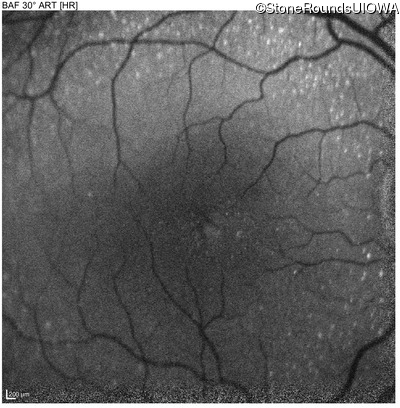

Blue Autofluorescence - Left - 20/50 -2

Exemplar